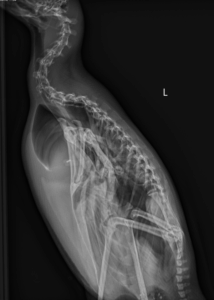

Penguins

Penguins also participate in radiographs, though their setup looks a little different. We perform standing radiographs, which is exactly what it sounds like—the birds stand upright inside a custom acrylic box designed just for them. One side of the box slides open for easy entry and exit, and many penguins waddle right in when it’s their turn.

Once they’re comfortably in place, we capture two images: a front-to-back (ventrodorsal) view and a side view. Occasionally, we pause for a moment while a penguin shifts into position, but with a little patience, the results are almost picture-perfect.